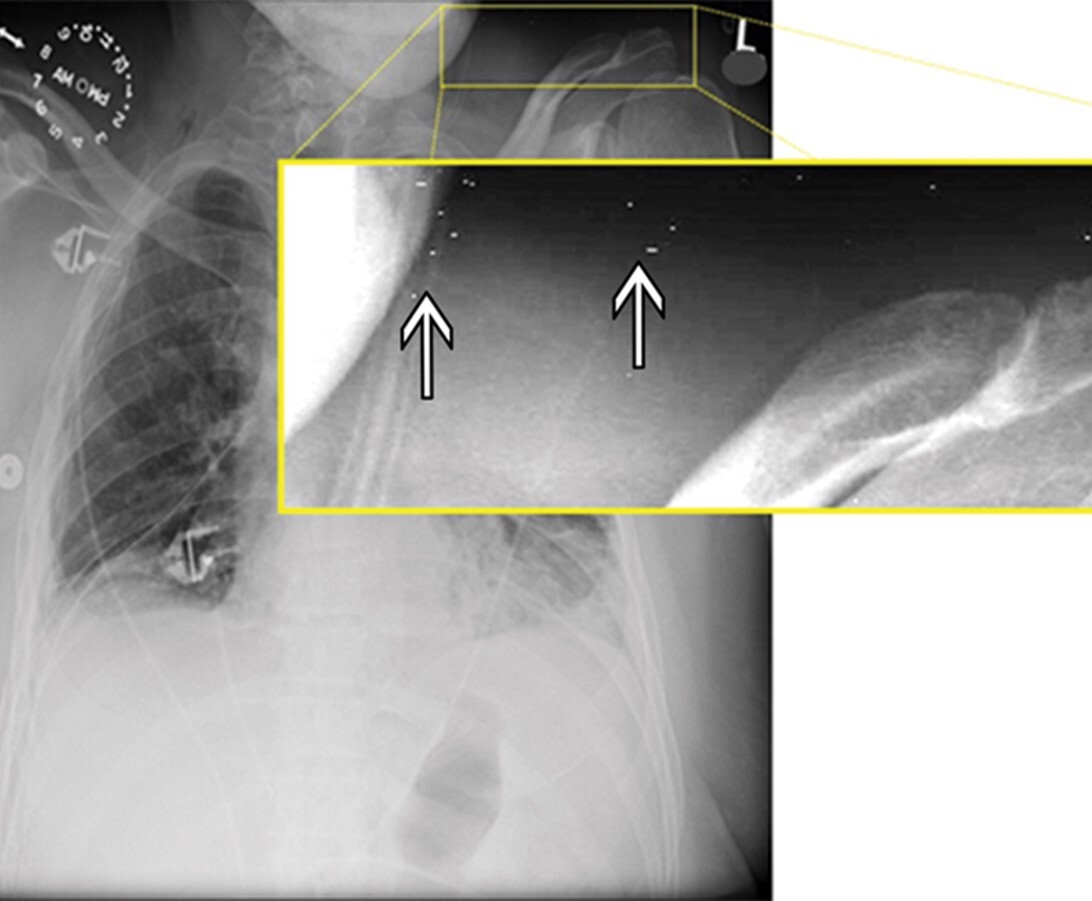

The attached image was obtained on a CR imaging system in the table bucky, using a grid frequency of 80 lines/cm and processed with a laser read out running perpendicular to the grid lines. The x-ray tube was centered, in focus and the gird was properly aligned.

What is the name of the alternating dark and light line artifact seen throughout the image?

A

Moire’ Pattern due to Aliasing

Would this artifact have occurred during image processing or image acquisition?

Image processing

State the cause of the artefact.

The sampling frequency/rate of the laser was less than double the desired maximum spatial frequency.